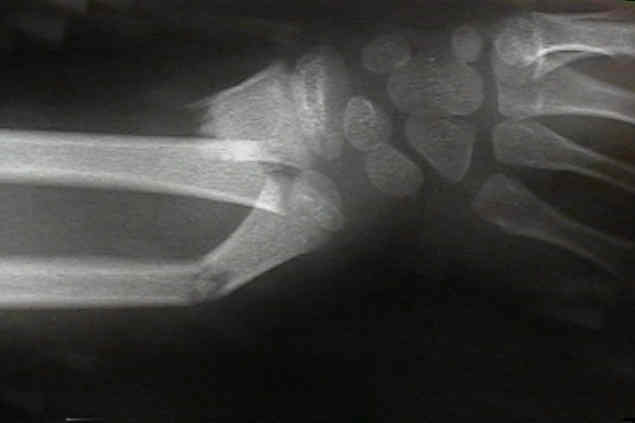

bayonette apposition

- generally bayonette opposition will require operative reduction (either closed with a Kapandji K wire levering technique or in some situations, an open reduction and fixation with K wires will be required);

- historically, overriding of a both bones forearm fracture was acceptable if...

- there was no deviation of radius and ulna toward each other;

- there was no encroachment of the interosseous space;

- pt is less than 10 yrs of age;

Displaced Distal Third Frx

- angulation up to 20-25 deg during first ten years is OK;

- angulation > 10 deg is unlikely to correct after 10 yrs